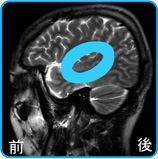

脳の左側面からのMRI脳画像

青○は、聴覚系脳番地の位置を示します。

ちょうど左右の耳の穴から4センチ上の位置に相当します。左右の耳に近い位置に左右の聴覚系脳番地があります。

左図から右図へ、酸素を使って活動している主な脳番地が移動することを伝達系から聴覚系への脳番地シフトといいます。